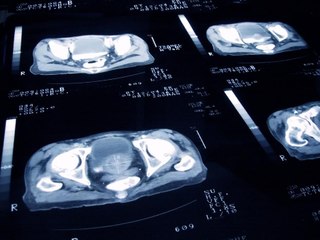

Milano, 10 lug. (askanews) - La cura per il tumore alla prostata ha un nuovo alleato. L'Agenzia Italiana del Farmaco (AIFA) ha riconosciuto la rimborsabilità per enzalutamide, farmaco anti-androgeno di nuova generazione che agisce sulle cellule tumorali del carcinoma prostatico. Una svolta per una delle patologie più diffuse tra gli uomini adulti. Abbiamo parlato con Pierluigi Bove, Professore Associato di Urologia, Dipartimento di Scienze Chirurgiche Università degli Studi di Roma Tor Vergata: "Il tumore della prostata è il primo tumore del sesso maschile. Questo vuol dire che per incidenza e prevalenza di malattia rappresenta la forma tumorale più frequente nel sesso maschile. Per fortuna per quanto riguarda la sopravvivenza e la mortalità i dati sono molto favorevoli. È un tumore frequente, con in Italia circa 7 mila nuovi casi-anno con una prevalenza di malattia di più di 600 mila pazienti affetti in questo momento di tumore alla prostata". I benefici di enzalutamide sono molteplici, un'efficacia del trattamento evidenziata in diverse fasi del carcinoma. Una delle novità rispetto ai trattamenti precedenti è l'impatto minore sulla sfera sessuale, non incidendo sulla produzione del testosterone e su altri aspetti della qualità della vita. È poi intervenuto Ugo De Giorgi, Professore Associato di Oncologia Medica Unisalento e Direttore SC Oncologia Universitaria Ospedale Fazzi - Lecce: "Enzalutamide è un antiandrogeno di ultima generazione, già impiegato in tumori prostatici e metastatici. In questo caso la nuova indicazione viene prima della comparsa delle metastasi a distanza. Per cui i pazienti che hanno comunque fatto un intervento sulla prostata o una radioterapia e che hanno una ripresa e un incremento del PSA. In questo caso lo studio ha dimostrato che il farmaco da solo o in combinazione con la deprivazione androgenica, che consiste nella castrazione farmacologica, è superiore rispetto alla sola castrazione castrazione farmacologica che al momento rappresenta lo standard terapeutico per questi pazienti". E a beneficarne è soprattutto la vita del paziente, della coppia e della famiglia intera. Curare malati e non malattie, mettersi al servizio dell'individuo per garantire benessere e prospettive di vita sana. Enzalutamide è pronta a far partire la rivoluzione.